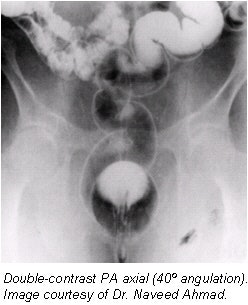

- A posteroanterior (PA) axial projection should include the rectosigmoid area (14 x 17-inch, or 36 x 40-cm IR). The PA projection with the patient in prone projection is preferred over an AP in supine as it results in a more uniform radiographic density of the entire abdomen. The entire colon, including the rectum, should be clearly seen.

- Overhead films. All overhead films must be taken at 110 kVp; additional air should be insufflated before taking decubitus projections (approximately 5-7 pumps before each decubitus). No post-evacuation film is needed. All overhead films are obtained with the table horizontal. Suggested films that should be obtained are:

- PA to include rectum (14 x 17-inch, or 36 x 40-cm IR).

- 15º RAO with 35º tube angle caudad for sigmoid (14 x 17-inch, or 36 x 40-cm IR); three overhead films and five on a gurney against an upright bucky.